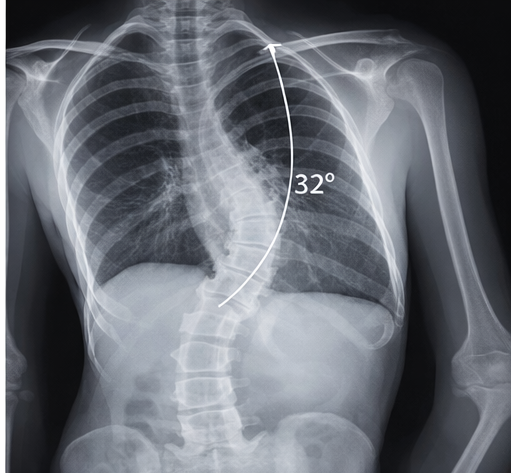

Standing posteroanterior and lateral radiographs of the whole spine revealed a right thoracic curve with a Cobb angle of 32° (T5–T11) and mild vertebral rotation.

Risser sign was grade 1, indicating significant remaining growth potential and risk of progression. No congenital vertebral anomalies were identified. Magnetic resonance imaging (MRI) was not indicated due to the absence of neurological signs or atypical curve patterns. Baseline pulmonary function tests were within normal limits.